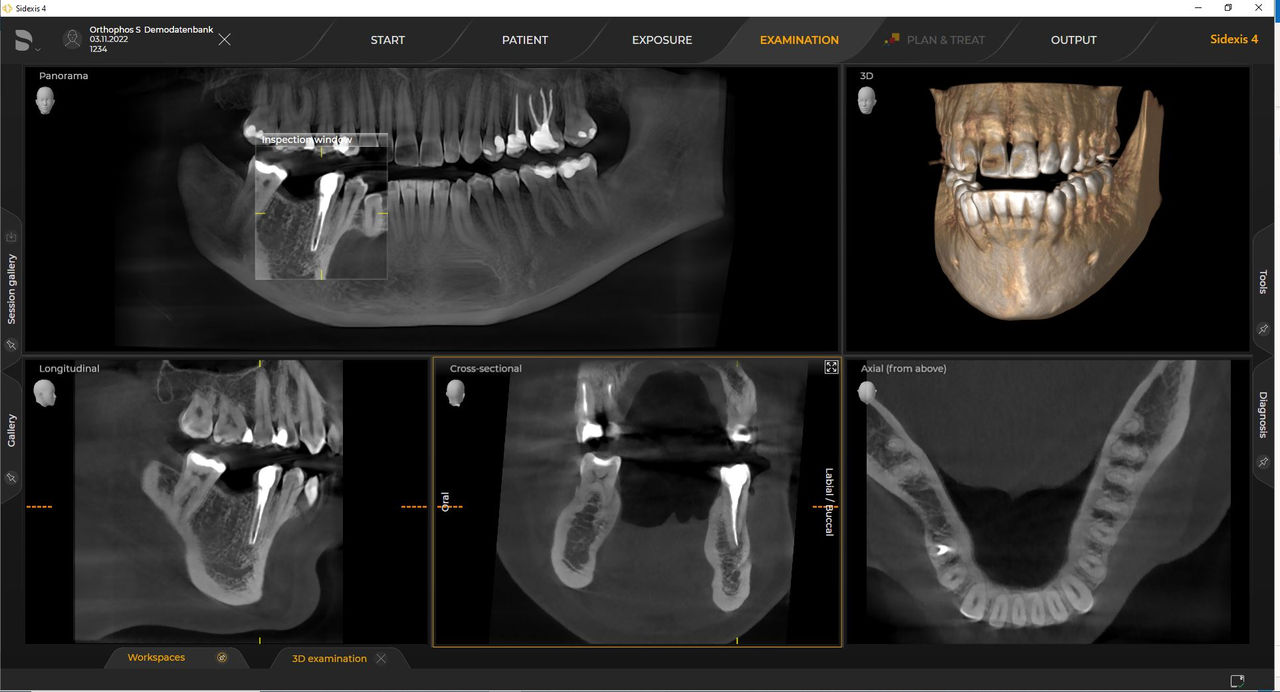

Urządzenia rentgenowskie firmy Dentsply Sirona współpracują wyłącznie z systemem Sidexis 4. Można łatwo przenieść dane z systemu Sidexis XG do systemu Sidexis 4. Sidexis 4 zapewnia pełną funkcjonalność cyfrową dzięki najnowszym narzędziom